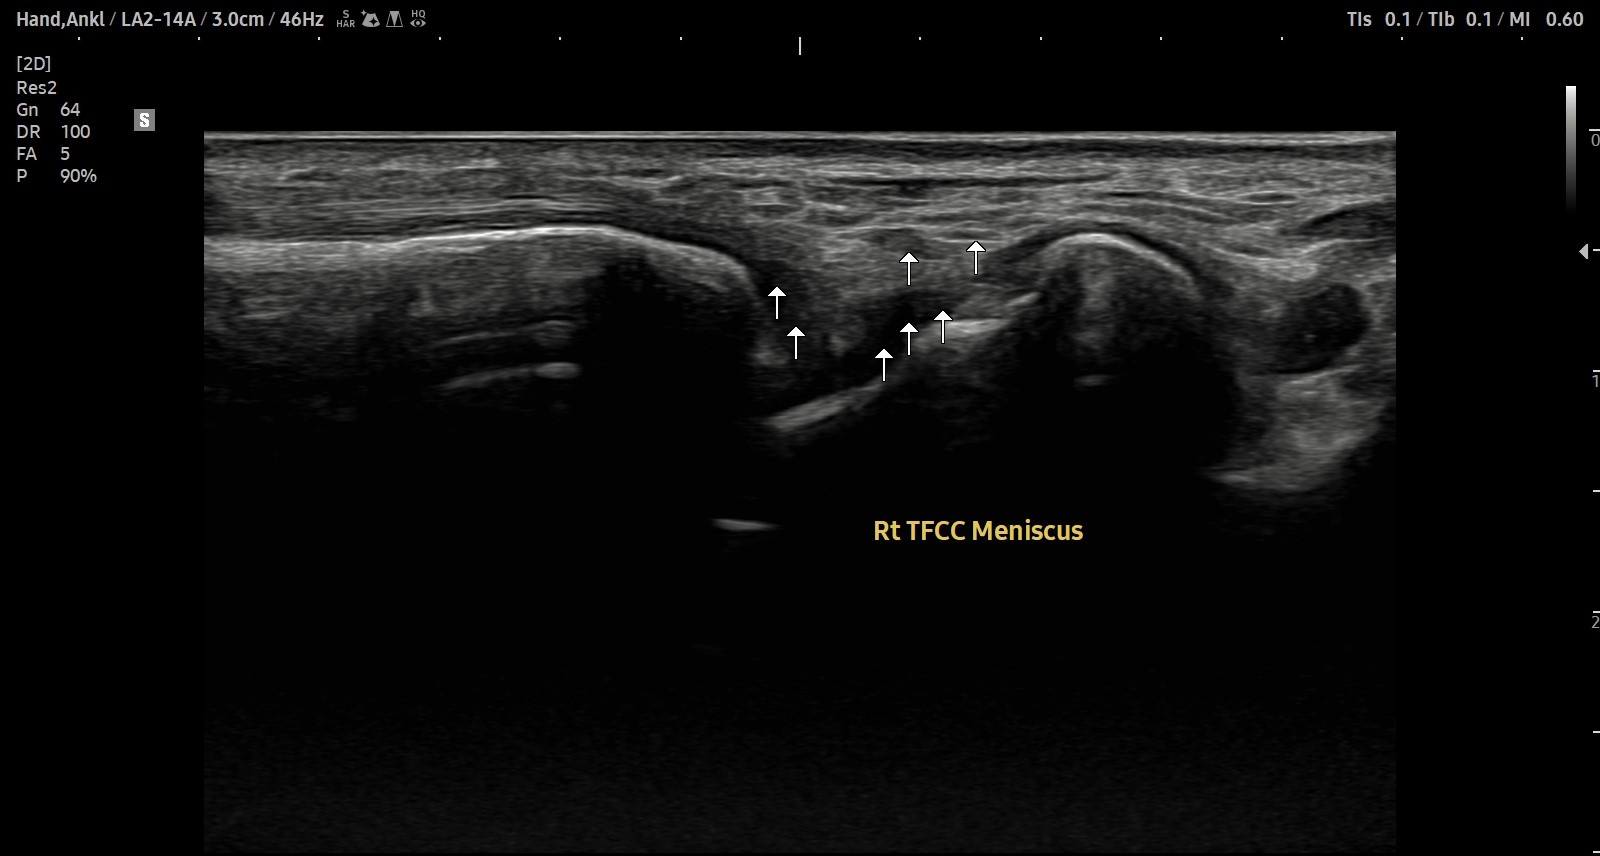

치료 후기에 사용된 전/후 검사 사진은 동일 인물의 결과이며 각 지점 동일 조건에서 촬영되었습니다.

개인에 따라 치료 결과에 차이가 있을 수 있으며, 부작용이 발생할 수 있습니다. 내원 후 충분한 상담을 받으시고 치료를 진행하시면 됩니다.

- 치료기간 : 25 .5 30 . ~ 25 . 6 .27

- 치료횟수 : 5 회(dna 1cycle)